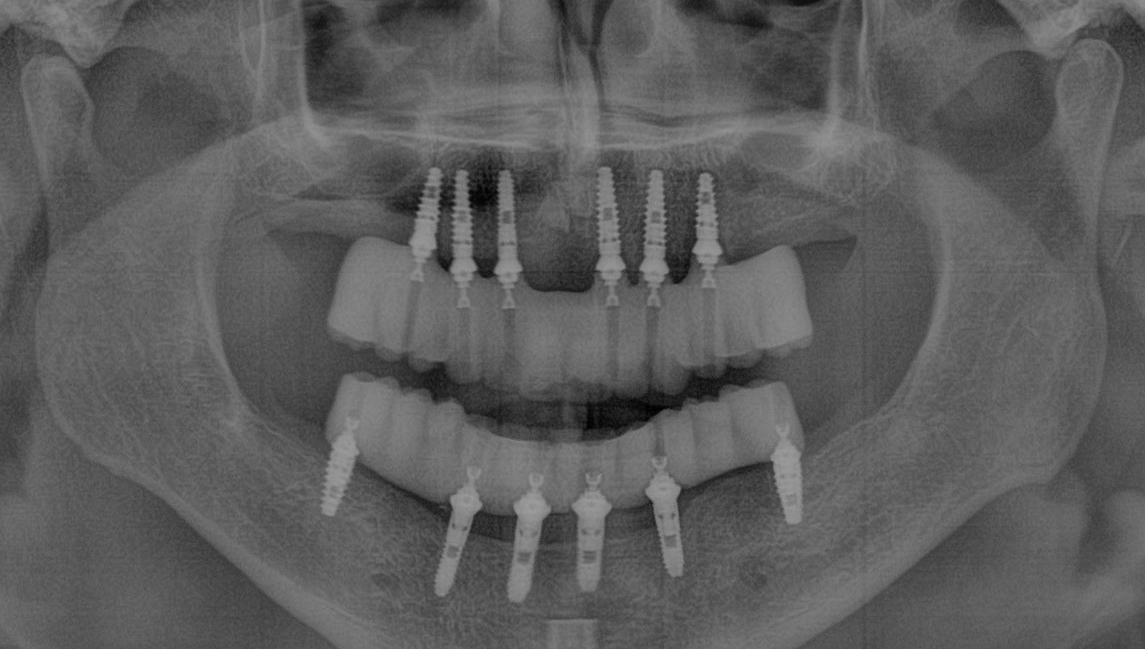

"He tenido múltiples servicios prestados, incluyendo la atención de rutina, extracción, implante, corona y protector bucal nuevo. El personal es profesional y amable ".- Sharon K. -

"El Dr. Pérez es un gran dentista".

"Me acaba de poner un implante y ha hecho un trabajo maravilloso".- Joyce C. -